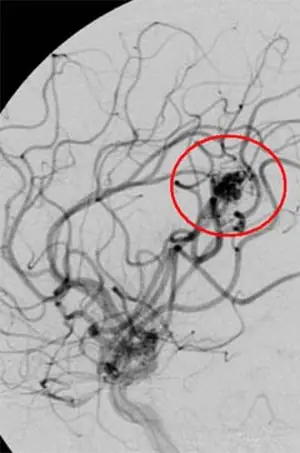

Лечение церебральной артериовенозной мальформации у 15-летнего пациента

Церебральная артериовенозная мальформацию до лечения

После лечения